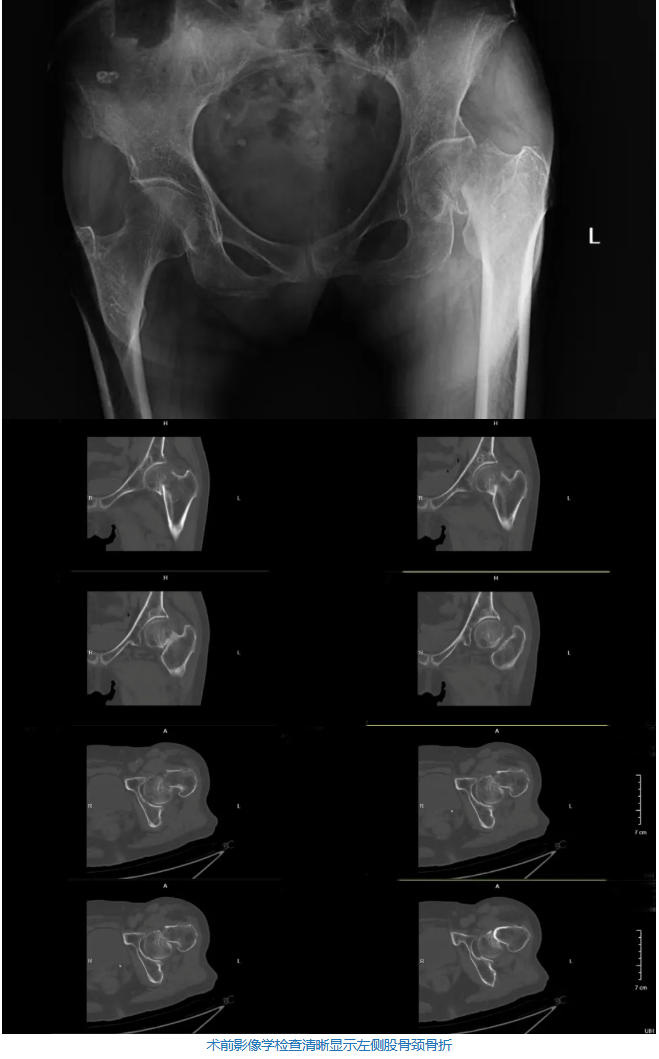

数天前,87岁的王奶奶(化名)不慎摔倒,导致左髋部剧痛,完全无法站立和行走。在家属的紧急护送下,老人来到了北医三院秦皇岛医院就诊。经过详细的术前检查,王奶奶被确诊为“左侧股骨颈骨折”。

然而,摆在医生和家属面前的难题,不仅仅是骨折本身。王奶奶的身体状况可以用“如履薄冰”来形容。病历显示,老人不仅患有重度骨质疏松,更合并了多项极其严重的心肺疾病:冠心病、主动脉及冠状动脉钙化;双肺气肿合并肺大泡、间质性肺病、慢性左下叶肺炎、肺结节;呼吸性碱中毒、左肾囊肿。